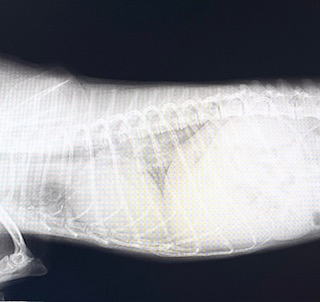

レントゲン検査…通常のレントゲン検査では肺は黒く写るが、肺炎になっている場合は白く写るので肺炎の重症度など見ることができる

○横から撮影したレントゲン画像

(それぞれ画像は左側が首側、右側がお腹側)

肺炎により異常を起こしている

(通常の肺と比べ黒い部分がない、または少ない)